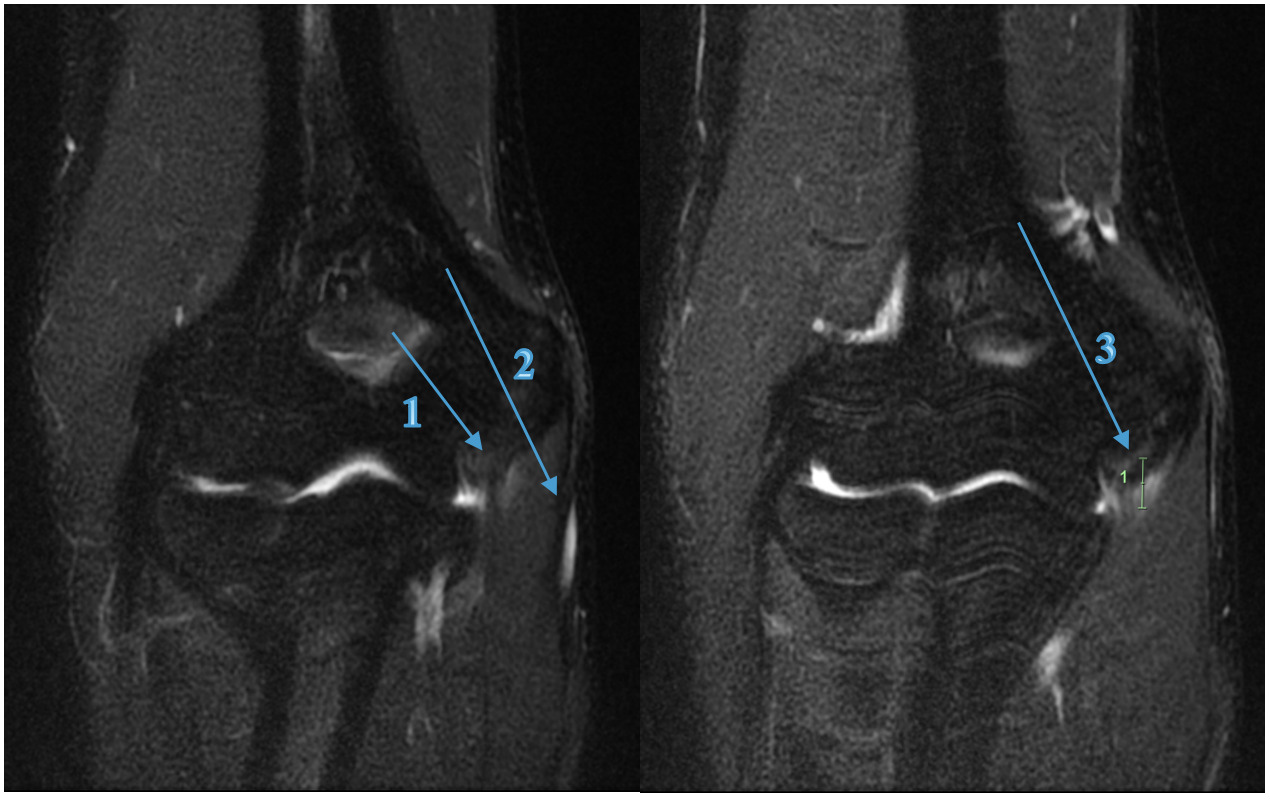

A 17-year-old amateur male Javelin thrower (State Representative) presented with right elbow pain which occurred during a competition 4 days prior. He described an audible pop and sharp pain experienced just before releasing the javelin. In the six weeks prior to the competition, the athlete experienced minor discomfort 3/10 (NRS) in the shoulder and medial elbow, which would ease at the completion of training and competition. As presented in Table 2 the physical examination findings, there was obvious swelling and palpatory tenderness over the medial elbow joint line (UCL/FCU & FDS tendons) and the medial epicondyle. The medial elbow dysfunction was exacerbated by any gripping or pronation motion reporting an 8/10 (NRS) at worst, reducing to 4/10 with the influence of ice, anti-inflammatories and analgesics as presented in Table 2 and 3. All activities ceased immediately until the pain and swelling was reduced. Due to the mechanism of injury and clinical findings, the practitioner referred him for MRI (Figure 3) which revealed a full thickness tear to the anterior bundle of the UCL with a low-grade partial tear of the FCU muscle, distal to the common flexor origin, which dictated the treatment choices and future modification to the training program.

MRI has typically been the gold standard imaging modality in identifying tendon and ligament pathology such as UCL injuries, particularly when full-thickness tears are present.10,51,52 Athlete A’s UCL injury was diagnosed by physical examination and confirmed by MRI (Figure 2), and Athlete D (Figure 3) also had diagnoses confirmed by MRI.